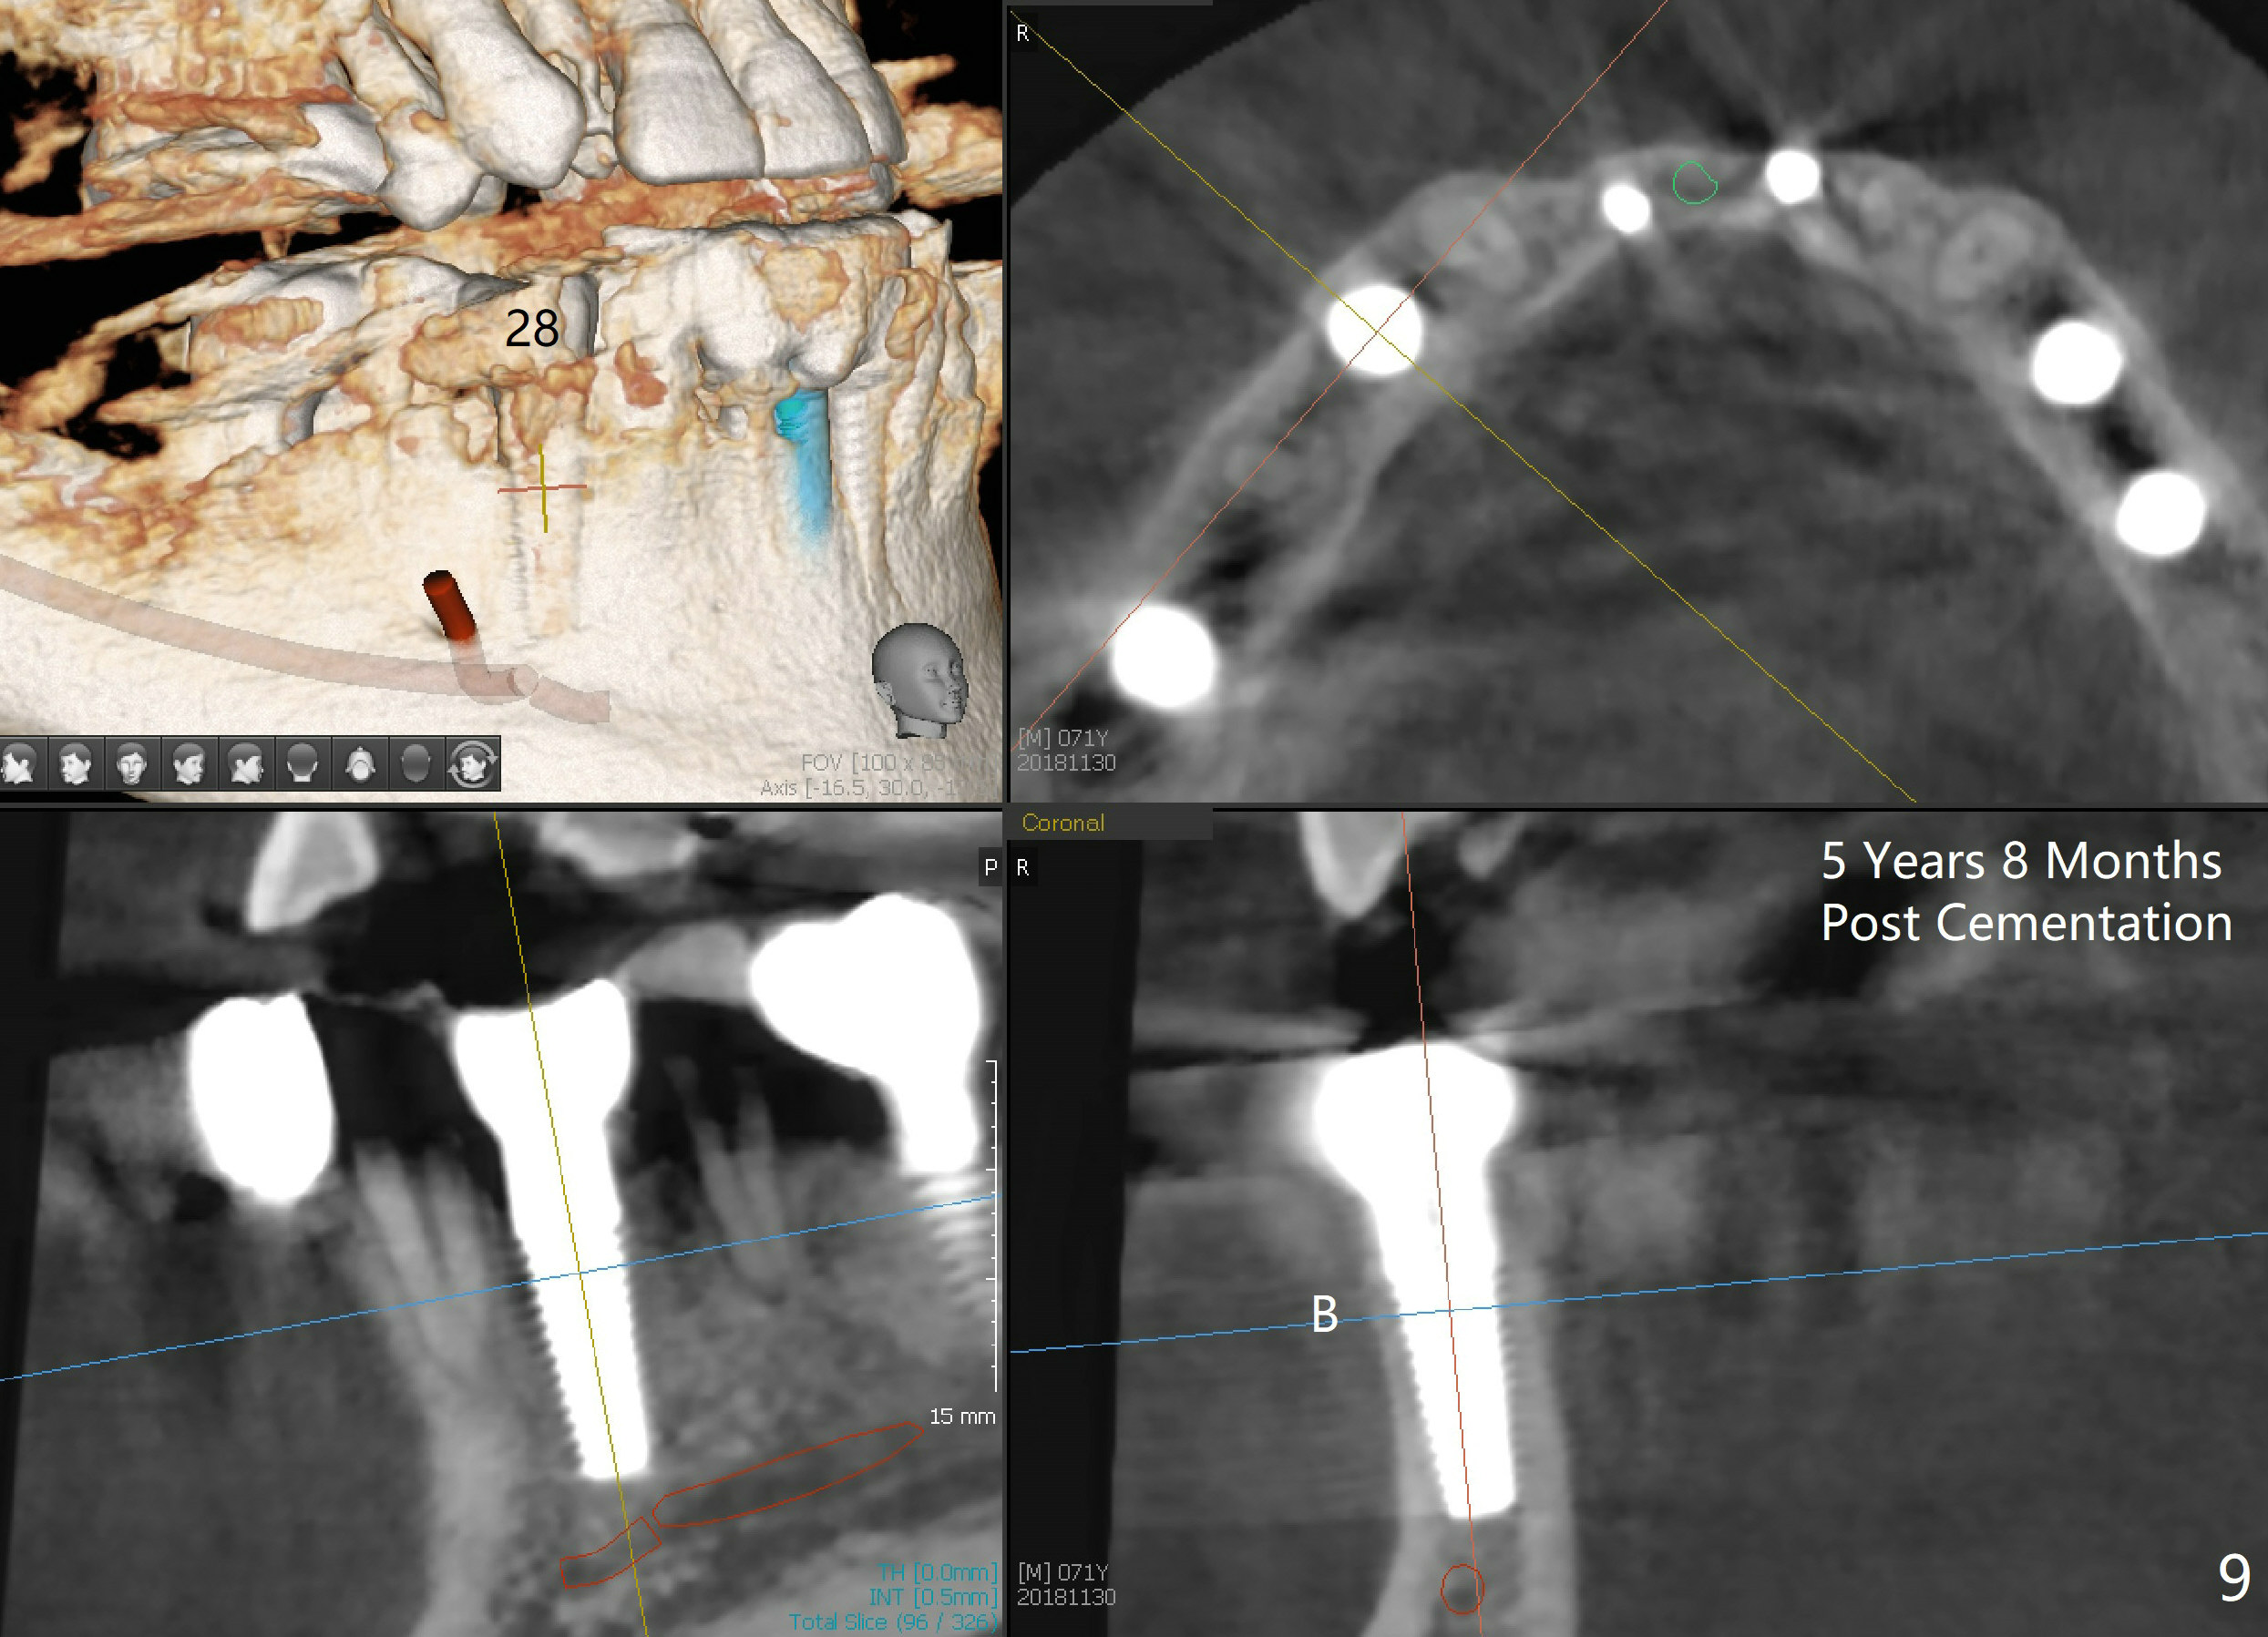

A 66-year-old man has poor dentition (Fig.1). Several teeth (x) including #28 need extraction and implants. The tooth #28 is extracted (Fig.2), followed by immediate implant (5x17 mm, Fig.3 I). There is more buccal gingival recession over the implant (Fig.4), which is less prominent 1.5 months postop (Fig.5). The definitive restoration is delivered less than 2 months postop (Fig.6), because of travel abroad. The patient agrees not to chew with the Emax crown. Five months later, he returns with chipped porcelain (Fig.7 arrowhead). It appears that immediate implant can survive early and over loading. More implants are necessary to share the masticatory loading. Since there is malocclusion, where to place implants appears to be critical (Model 3 30 4 5 6 7). There is no bone loss 4.5 years (Fig.8) or 5 years 8 months (Fig.9) post cementation.